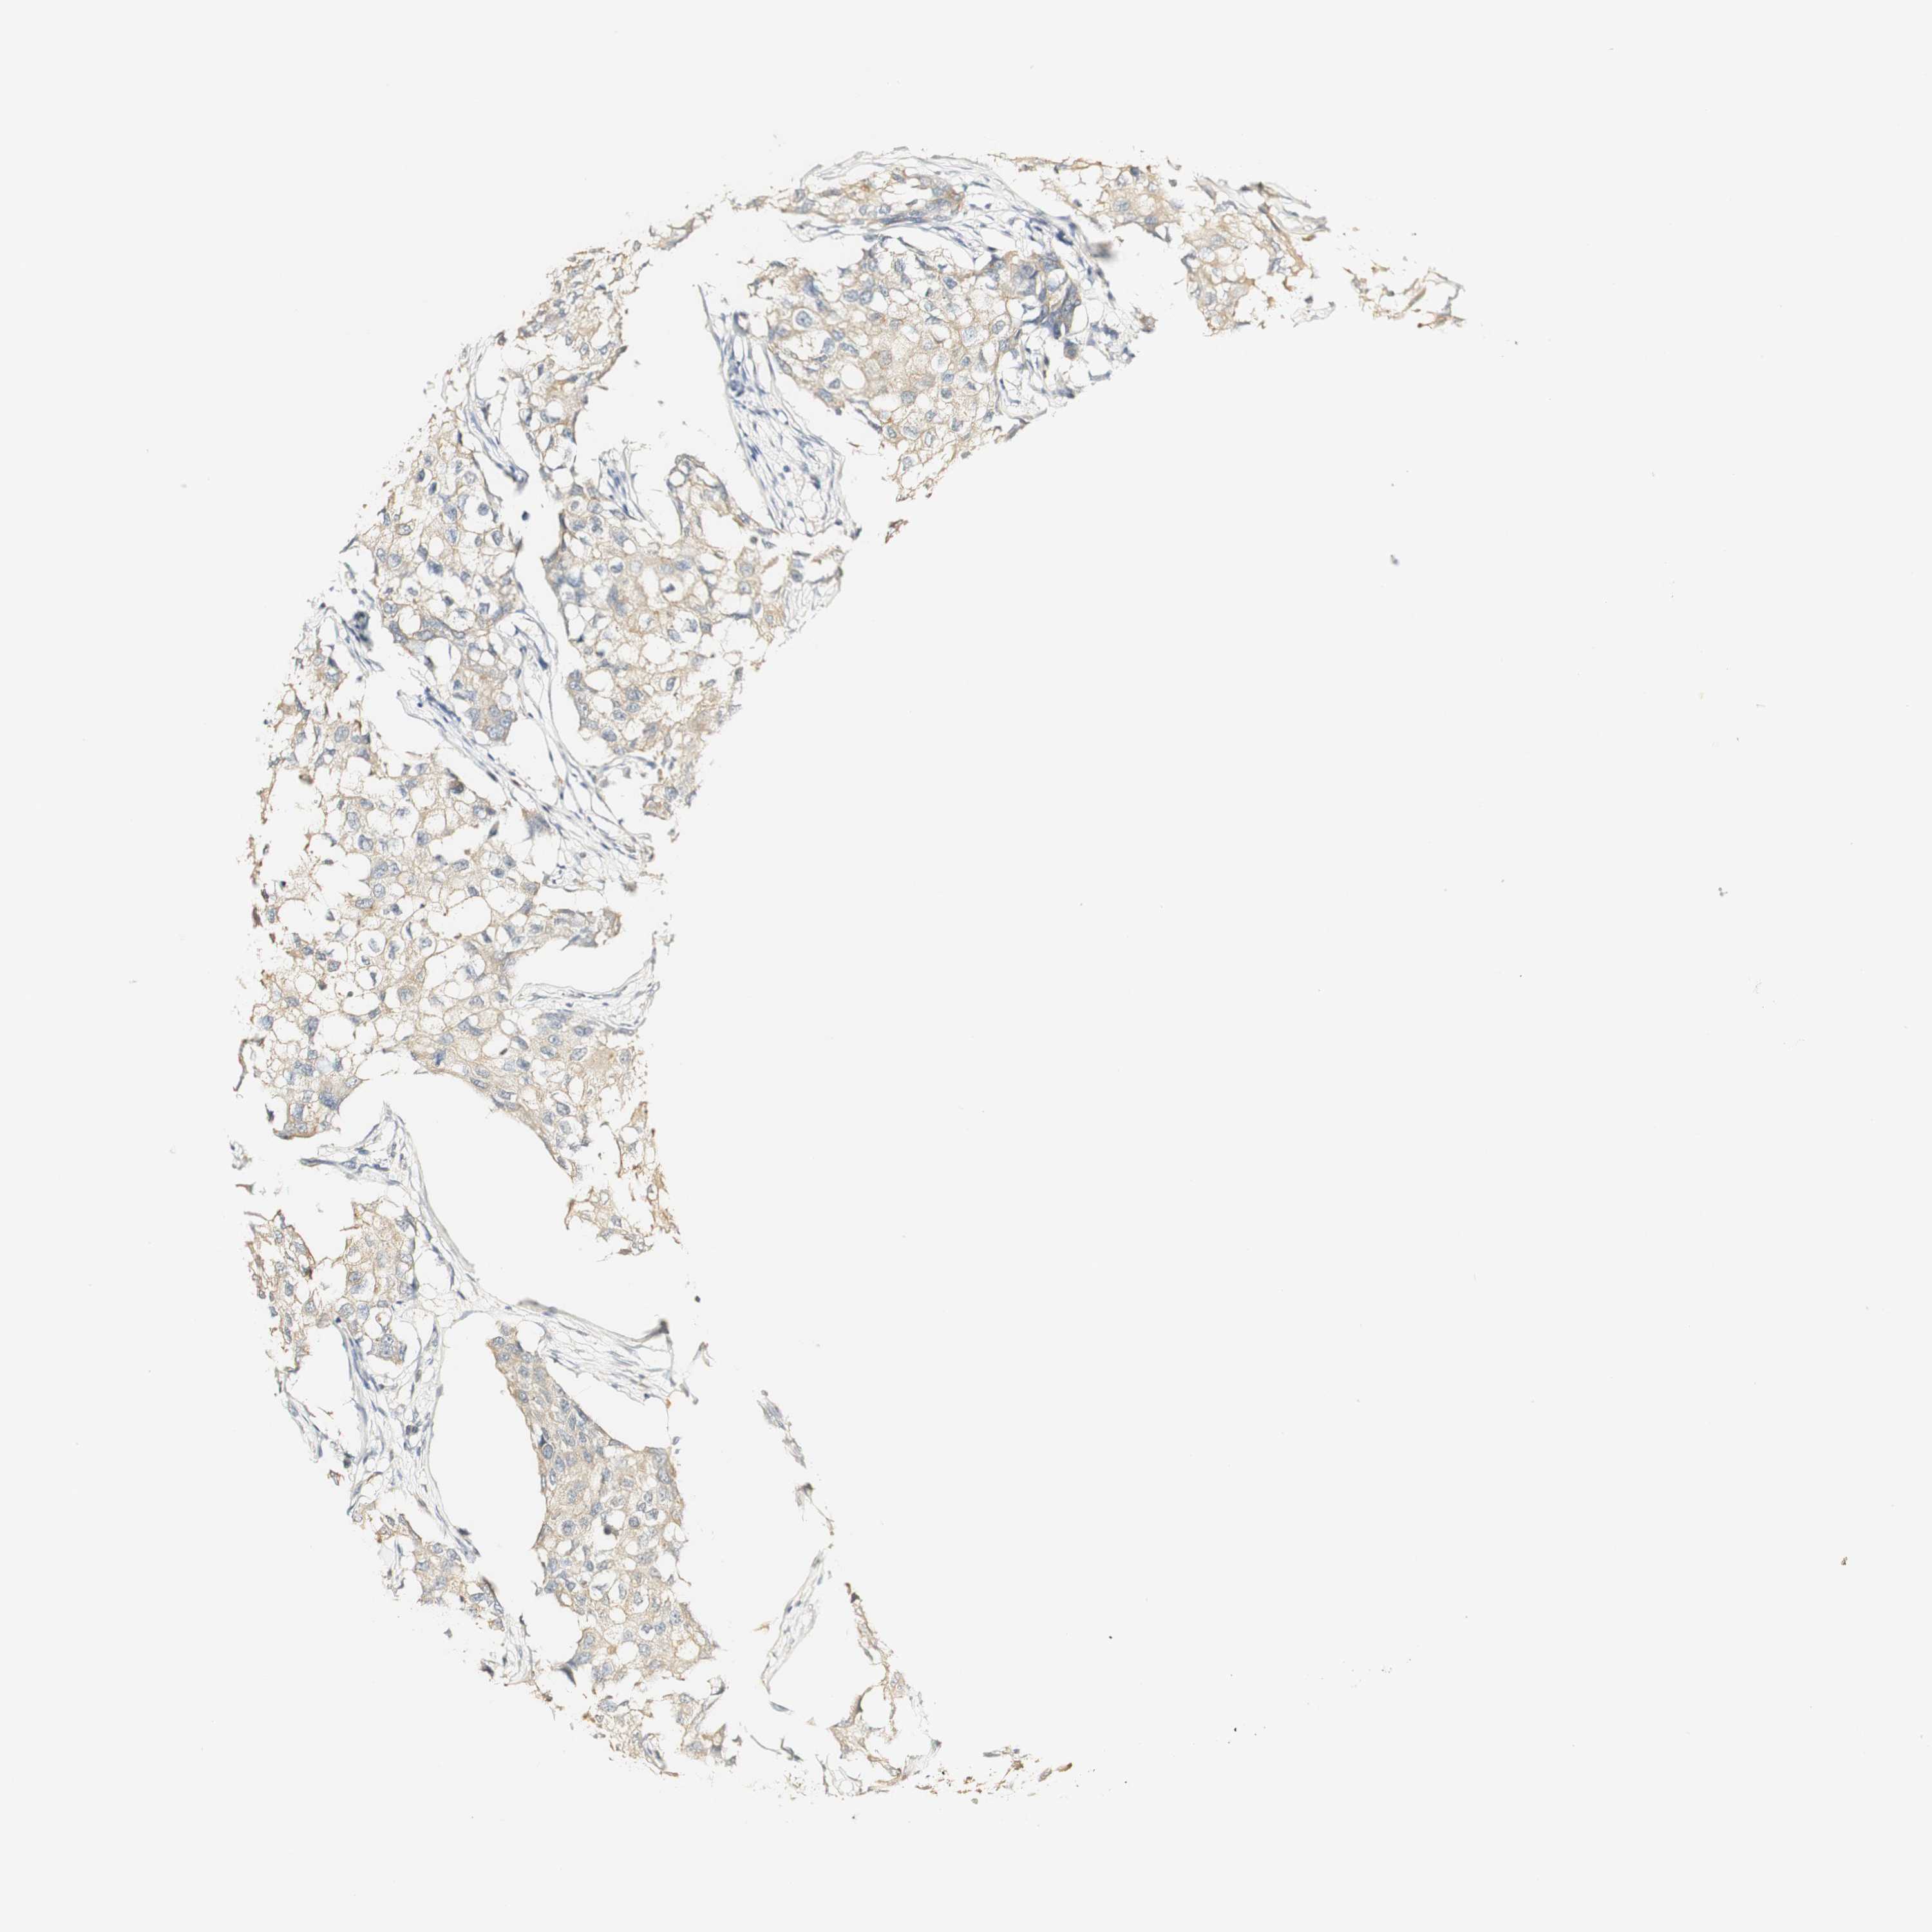

BRCA TCGA BRCA VALIDATION PROTEIN EXPRESSION

Breast cancer

Human cancer

Breast invasive carcinoma